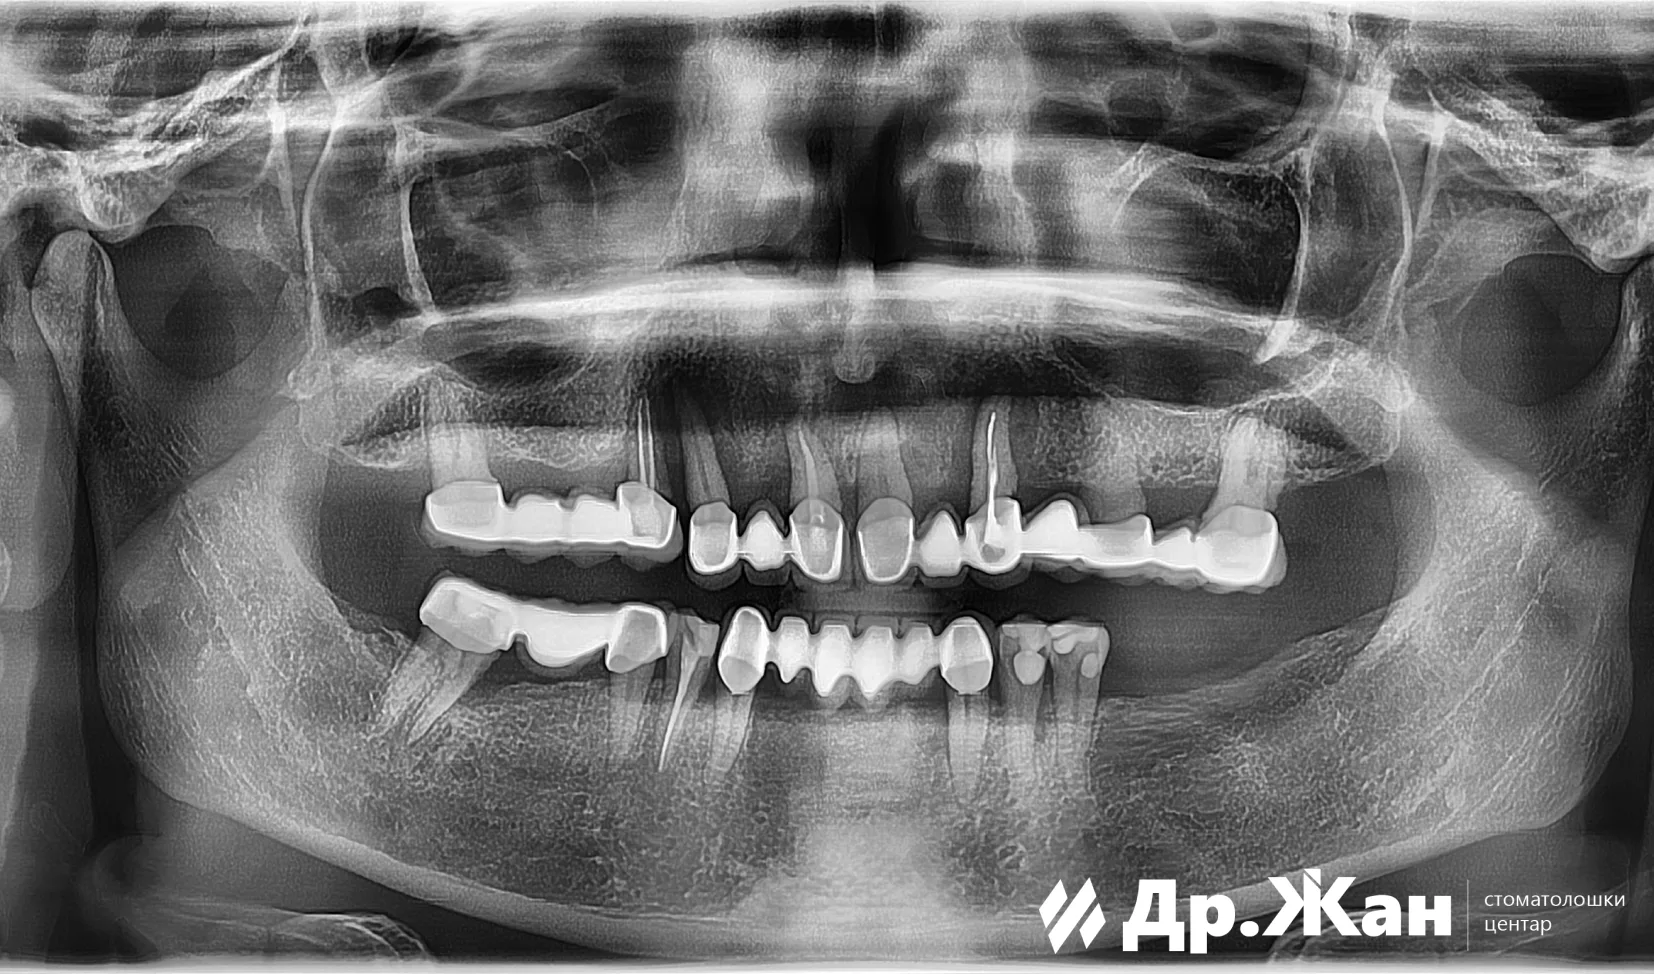

Оваа жена дојде во нашата ординација со нефункционален металкерамички мост во горната вилица. По првичниот преглед и денталната томографија, беше обезбеден план за терапија. За жал, тој вклучуваше отстранување на сите заби во горната вилица, но за среќа со нашето All on 6 решение ѝ помогнавме повторно да се насмевне.

ПРЕД